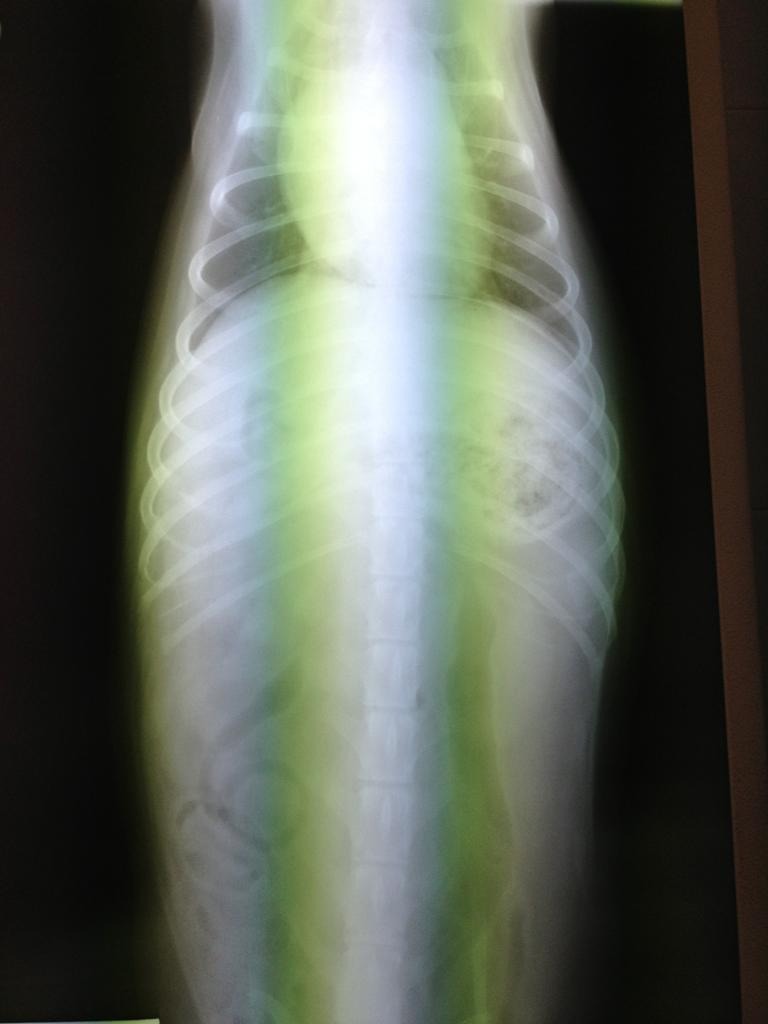

Ciao Mandy: dagli rx posso dirti al 99% che non è tumore...non li vedo...ed hai fatto stra bene a mandarmi le due proiezioni.

A questo punto però dovrei farti io alcune domande: 1) Difficoltà a respirare hai detto: fa fatica ad inspirare o ad espirare? 2) tossisce? 3) Hanno rilevato soffi cardiaci? Io, visto che dici essere peggiorato negli ultimi mesi, inserirei nella terapia (non vorrei però passare sopra i medici che lo stanno curando, quindi il mio è un consiglio nel massimo rispetto di colore sono li col cane, non potendolo io vedere) un diuretico. Il quadro polmonare mi sembra ascrivibile ad un edema polmonare. Quindi in tal caso darei Lasix o Diuren alla dose di 2 cpr ogni 12 ore. Questo lo darei anche senza avere le 3 risposte alle domande di cui sopra. Il profilo cardiaco mi sembra aumentato di dimensione..... Fammi sapere!!! I morti li portano via freddi.

Ho letto ora i tuoi commenti alle foto.....ero concentrato sulle radiografie.

Bene allora.....ma se ripeggiora, il diuretico lo darei lo stesso. Se l'animale mangia non ha effetti collaterali.... I morti li portano via freddi.

Non ti è arrivata la mail? Infatti mi sembrava strano che non mi avessi risposto. Te la incollo qui. 1. Entrambi 2. No 3. No Martedì sera gli hanno fatto una puntura di analgesico e una di un anti infiammatorio e con quelle è passato il peggio. Sembrava che stesse annegando. Siccome nella lastra si intravede un pezzo di osso nello stomaco pensano adesso che avesse avuto un gran dolore allo stomaco e respirava male per quello. Adesso sta bene il piccolo highlander. Aggiungo il diuren? |